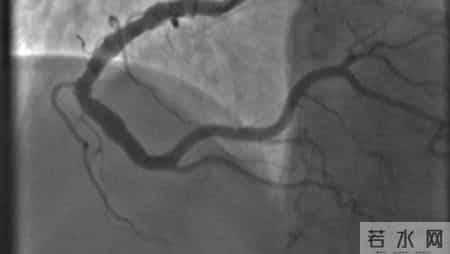

第一项:冠状动脉CT造影——看清血管堵没堵很多人以为只有胸痛了,才需要查心脏。但实际上,冠心病的可怕之处在于“无症状”。

冠状动脉CT造影(CTA)是一项无创检查,能清晰看到心脏血管有没有斑块、狭窄,甚至提前发现“未来可能堵住”的地方。

有一项发表在《中华心血管病杂志》的研究显示:超过60%的冠心病患者,在CTA发现明显狭窄前,并没有任何不适感。也就是说,等到你胸口闷了,可能已经堵了七八成。

所以,即使没有症状,只要你是高危人群,比如曾经得过冠心病、做过支架、三高患者或家族有心脏病史,就应该定期做CTA,早发现,早处理。